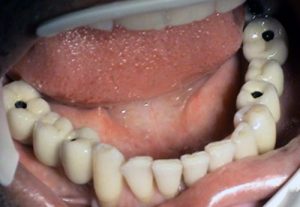

3. PHASE – prosthetic fabrication of temporary crown on implant

3. PHASE – fabrication of temporary solution